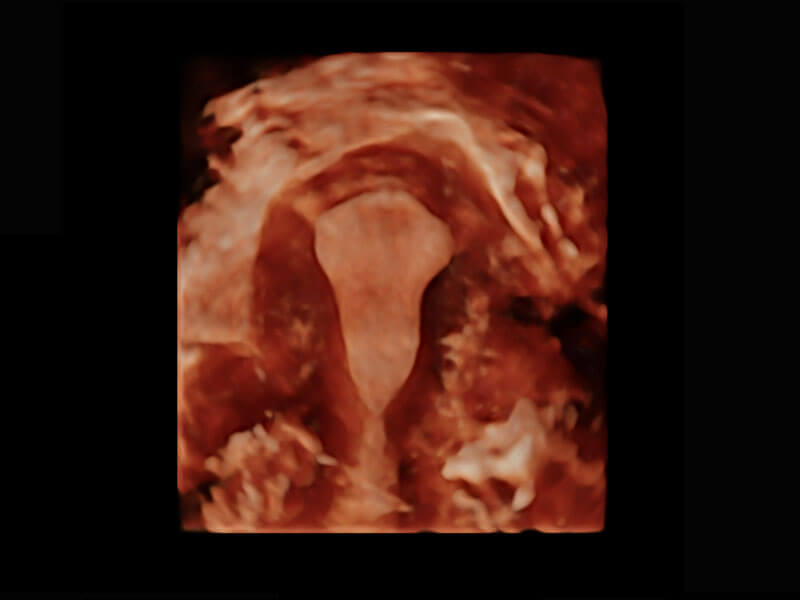

腔内三维-宫内节育器